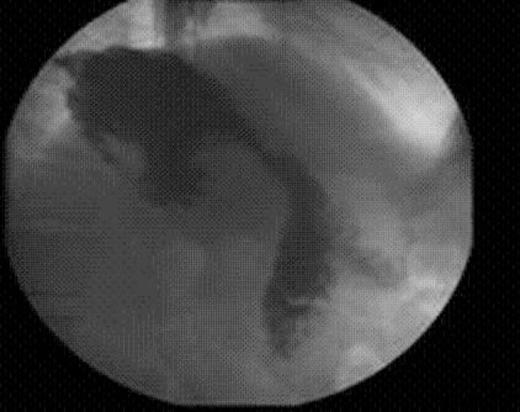

Upper GI Series 2 months after endoluminal gastric pouch plication

The patient was discharged home the next day. Six weeks after the procedure, the patient had lost 12kg in weight and no longer complained of any dumping syndrome. An upper GI series x-ray obtained 2 months after the pouch plication procedure revealed reduction in the size of the gastric pouch and a delay in emptying of contrast from the gastric pouch into the jejunum.